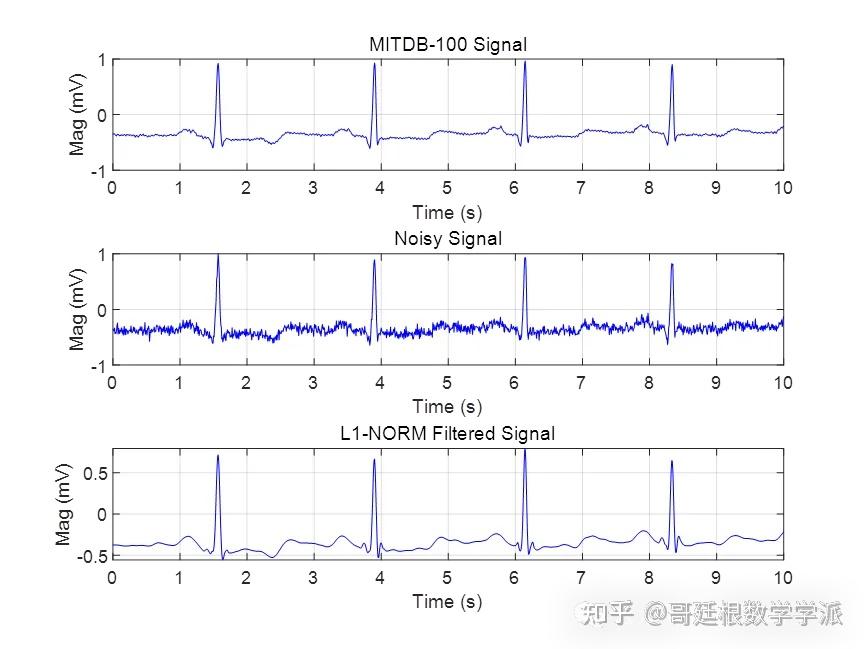

基于L1范数惩罚的稀疏正则化最小二乘心电信号降噪方法(Matlab R2021B)